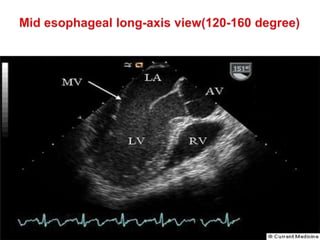

 The third mid esophageal view recommended for AV assessment is

the (AV) long axis (LAX) view; this is similar to the left ventricular

LAX view but may require further manipulation to ensure the

appropriate cut through the valve and proximal aortic root (i.e., with

the root being imaged in as close to horizontal projection as

possible).

 Starting from the SAX view the image sector depth is again

increased to assist orientation.

 The image plane angle is then rotated between 120° and 160°

(although image may be acquired at angles 100–120°) with or

without some manual anticlockwise rotation being applied. Then the

sector depth is reduced to give a close up of the valve and proximal

root .